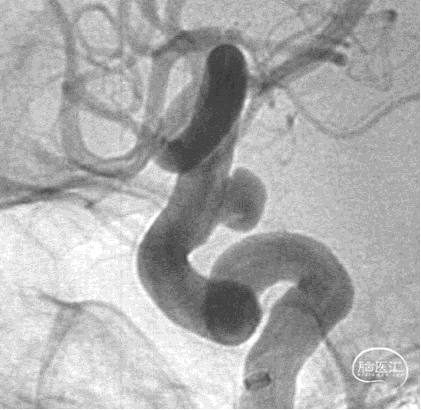

治疗结果

术后半年复查

2、患者同侧大脑前动脉A1段有小泡突起,术中将FD盖住同侧A1,以此减少A1血流量,降低小泡进一步变大及破裂风险。

5、FD植入后,动脉瘤明显造影剂瘀滞,效果显著。

7、术后半年复查动脉瘤治愈,且未发生支架远近端狭窄及内膜过度增生,治疗效果满意。

8、同侧A1动脉瘤在FD保护下无变化。